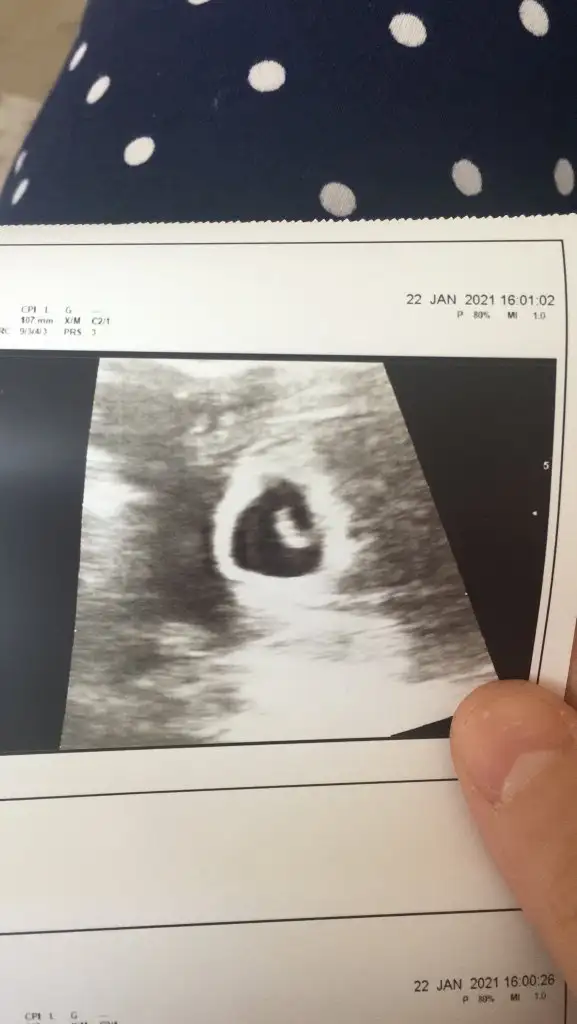

Ahahah bende yeni yeni öğreniyorum inan Canım kız bence (Eğer Vajinal ultrason görüntüsüyse erkek) B bitkiselhayat sende yorumlar mısın canım